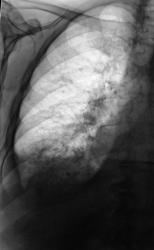

Двустороняя нижнедолевая плевропневмония (возможно застойного генеза), формирующееся левосторонее паракостальное осумкование.